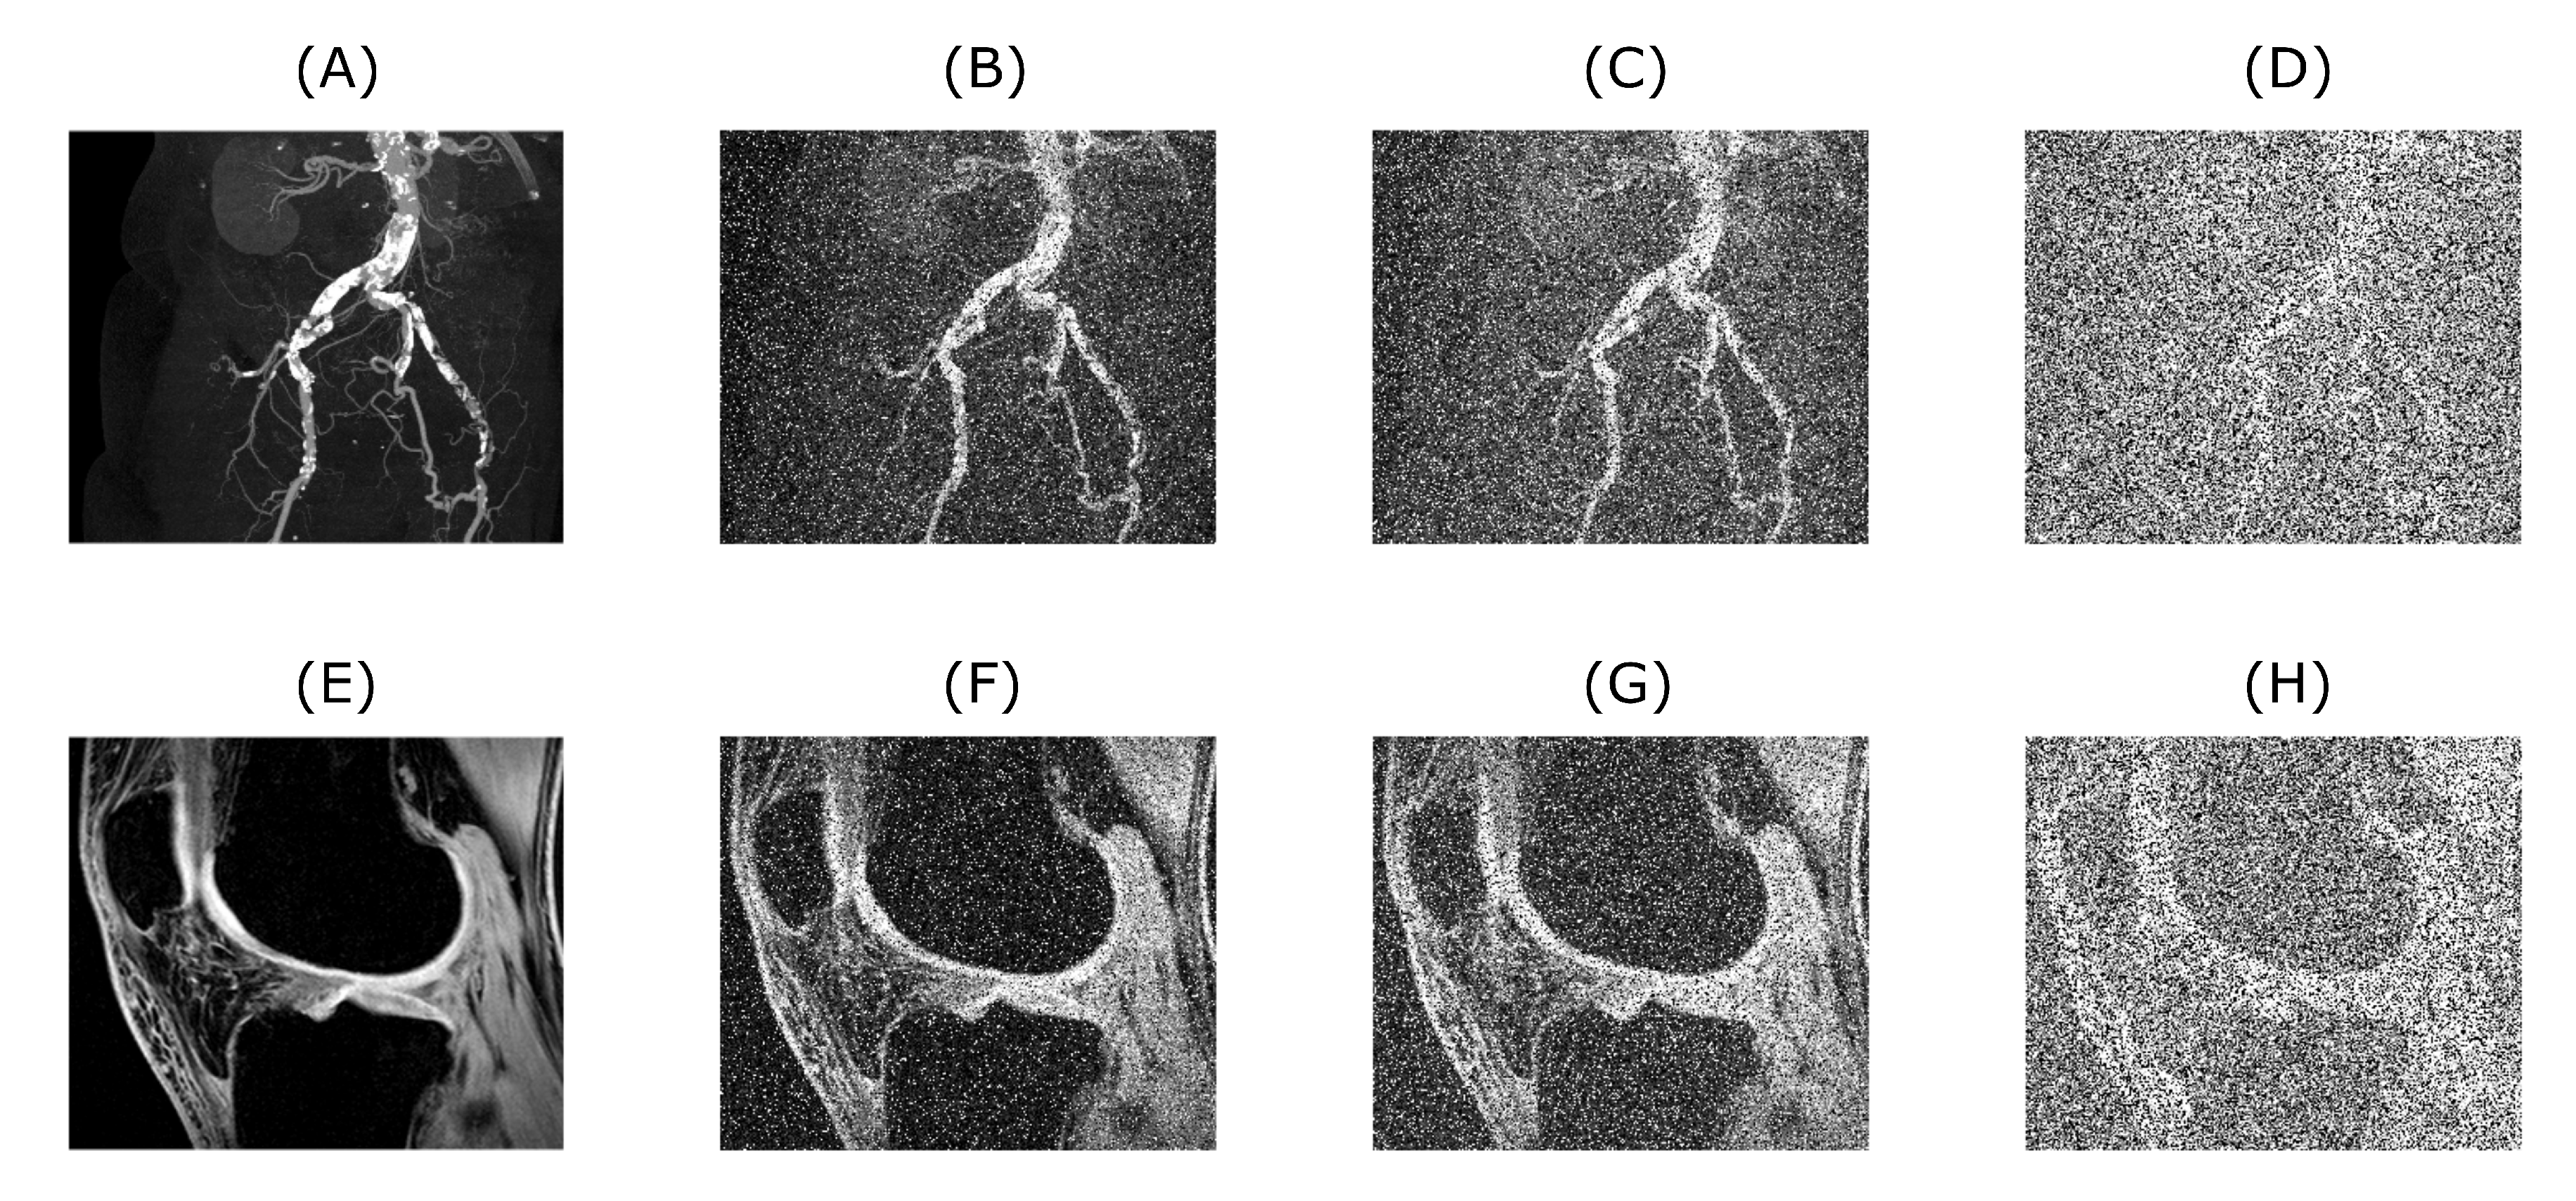

Figure 4 and Figure 5 demonstrate the relationship between the original input image, the image with added artificial noise and the denoised image. In these specific cases, both variables (mean value of AWGN and density of salt and pepper noise) governing the amount of an artificial noise were set to 0.35. Low-in value of the image adjust function was set to 0.45 and 0.4, for CT and MRI image, respectively. As two specific images are chosen from the range of the batch dataset, the image adjust function parameter is tweaked to achieve better performance. Algorithms 1 and 2 below describing procedure for solving a problem, based on conducting a sequence of a denoising for 1D a 2D signals.

Figure 2. Upper row is showing a CT scan of blood vessel calcification with the native level of noise (A) used as an input for algorithm testing. Images (BD) are showing the original image with added artificial noise for 0.1, 0.2 and 0.5 level (in fact the noise consists of a sum of three noise types, in which the number means a mean value for additive white Gaussian noise and density for salt and pepper noise, speckle noise is kept on a constant default value used in MATLAB), respectively. Lower row shows the example of MRI scan of knee cartilage (E used as an input), again with different consecutive noise levels of corresponding magnitude (FH).